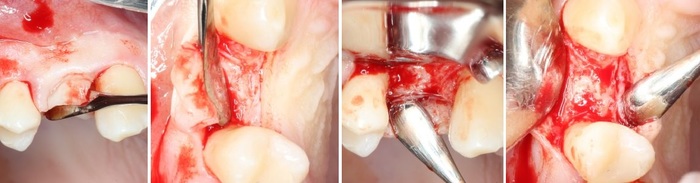

Имплантация начинается с разметки. Проводится это при помощи шаровидного бора

Далее, с помощью пилотной фрезы диаметром 2 мм задаётся ось лунки будущего имплантата, которую контролируем при помощи пинов*

*Штуковина для контроля положения имплантата

Далее, коль ось лунки задана правильно, нам остаётся лишь довести лунку до нужного диаметра. Для этого используются основные рабочие фрезы. Первая из них — диаметром 3.0 мм:

После чего — контроль положения с помощью входящих в набор аналогов имплантатов

На очереди следующая фреза, диаметром 3.4 мм:

И теперь на очереди самый ответственный этап — финишная фреза для нашего имплантата диаметром 3.8 мм. Теперь мы понижаем обороты на физиодиспенсере до минимума, чтобы избежать перегрева и травмы костной ткани, после чего очень-очень аккуратно проходим лунку:

Еще раз проверяем все с помощью аналогов имплантата. Как говорится, семь раз отмерь, один воткни:

Мы довели лунку до глубины 11 мм и диаметра в 3.8 мм. Но на этом подготовка лунки не заканчивается.

А всё потому, что костная ткань — упругая среда, и чтобы снять напряжение с кортикальной пластинки (и предотвратить периимплантит) мы используем специальную кортикальную фрезу:

При работе с очень плотной костной тканью мы дополнительно используем специальный метчик: